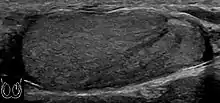

Epididymo-orchitis in a 77-year-old man. (a) Transverse sonography shows enlargement of the epididymis with hypoechogenicity noted over the testis and epididymis associated with scrotal wall thickening. (b) Color Doppler sonography showed hyperemic change of the testis and epididymis, presenting as an “inferno” vascular flow pattern.

Epididymitis and epididymo-orchitis are common causes of acute scrotal pain in adolescent boys and adults. At physical examination, they usually are palpable as tender and enlarged structures. Clinically, this disease can be differentiated from torsion of the spermatic cord by elevation of the testes above the pubic symphysis. If scrotal pain decreases, it is more likely to be due to epidiymitis rather than torsion (Prehn's sign). Most cases of epididymitis are secondary to sexually transmitted disease or retrograde bacteria infection from the urinary bladder. The infection usually begins in the epididymal tail and spreads to the epididymal body and head. Approximately 20% to 40% of cases are associated with orchitis due to direct spread of infection into the testis.

At ultrasound, the findings of acute epididymitis include an enlarged hypoechoic or hyperechoic (presumably secondary to hemorrhage) epididymis [Fig. 20a]. Other signs of inflammation such as increased vascularity, reactive hydrocele, pyocele and scrotal wall thickening may also be present. Testicular involvement is confirmed by the presence of testicular enlargement and an inhomogeneous echotexture. Hypervascularity on color Doppler images [Fig. 20b] is a well-established diagnostic criterion and may be the only imaging finding of epididymo-orchitis in some men.